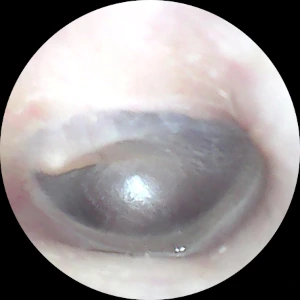

< (좌) 프렌젤 후, (우) BTV로 42.4m 다녀온 후 >

위 사진은 다이빙 후 귀내시경으로 촬영한 고막 상태를 보여줍니다. 왼쪽 사진은 프렌젤 후 촬영한 것으로, 고막 테두리와 망치뼈 부분이 충혈된 모습을 확인할 수 있습니다. 반면, 오른쪽 사진은 BTV로 42.4m 다녀온 후 촬영한 것입니다. 고막이 스트레스를 받지 않고 깨끗한 상태를 유지하고 있음을 알 수 있습니다. BTV로 40m를 넘게 가더라도 고막에 손상을 입을 가능성은 거의 없습니다.